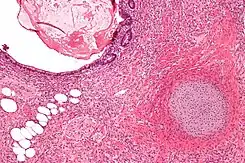

Micrografía de un teratoma con componentes gastrointestinales (arriba a la derecha) cartílago (abajo, a la derecha) y tejido adiposo (abajo a la izquierda). Tinción con hematoxilina-Eosina.